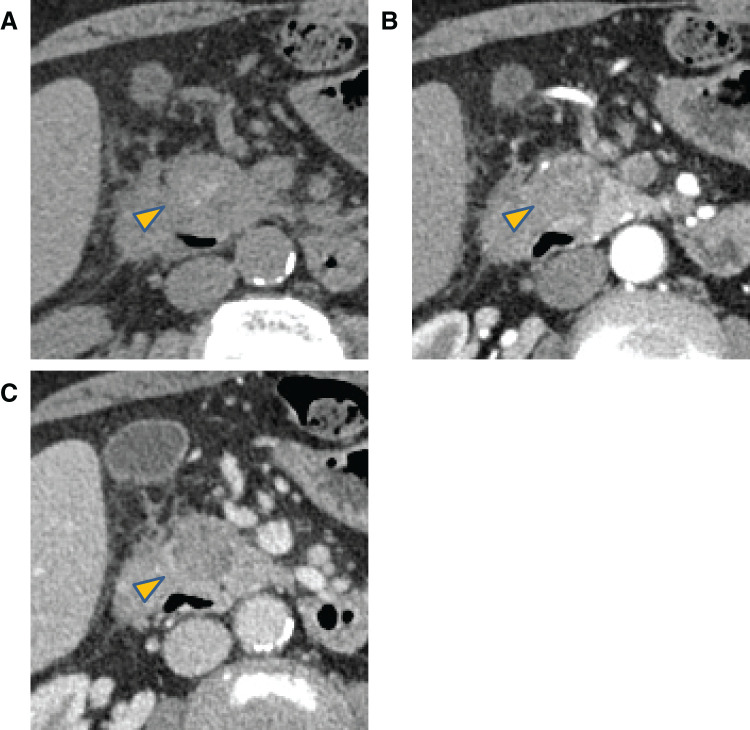

Case presentation: A 64-year-old man presented with groove pancreatitis attributable to heavy alcohol consumption and a hypovascular mass in the groove area with duodenal bleeding. The lesion, which was initially considered a pancreatic groove tumor with groove pancreatitis, was treated with subtotal stomach-preserving pancreaticoduodenectomy. However, a post-surgical pathological analysis revealed that it was a pancreatic pseudocyst in the groove area containing bilirubin calcium stones and pancreatic stones.

Conclusions: Cases comprising fistula formation in the common bile duct are rare. A pancreatic pseudocyst that formed a fistula with the common bile duct was suspected in the present case. This case was unique because the pseudocyst was filled with microbiliary stones. This report highlights the difficulty in differentiating a pseudocyst filled with bilirubin calcium stones from a neoplastic lesion and underscores the importance of the accurate diagnosis and management of this rare pathology.